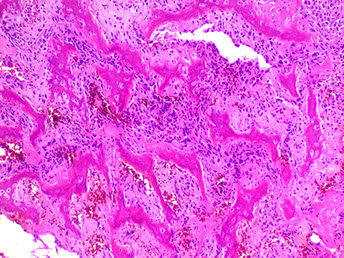

Micro: malignant bone stroma with lacy-patterned matrix that at least focally produces osteoid surrounding neoplastic mesenchymal cells and is infiltrating the marrow spaces bwt mature trabeculae

- can see atypical mits (atypical mits NEVER in b9 conditions [?])

- normalization: atpia is less in oseoid islands than in surrounding malignant stroma

Any amount of neoplastic matrix automatically upgrades a lesion to osteosarcoma

MC subtype is conventional high-grade type (made mostly of osteoblastoma; 75-85%); then high-grade secondary osteosarcoma (10%) and surface osteosarcoma (5-10%) - [chondroblastic {makes cartilage}, fibroblastic {no matrix production}, small-call or giant-cell rich]

Osteosarcoma